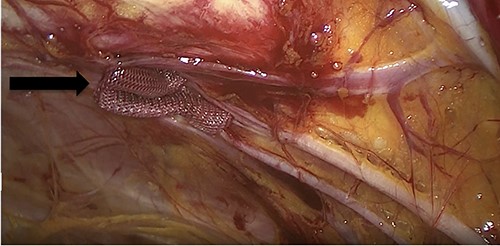

Due to the high-grade small bowel obstruction, the patient was pushed as an emergency case to the operating room. The surgery started and ended as a laparoscopic procedure with three small incisions; 12, 11 and 5 mm port sizes located supraumbilically, right and left midclavicular line relatively. Once the peritoneum was penetrated, and gas insufflated, diagnostic laparoscopy was done, and the obturator hernia with bowel content was visualized (Fig. 3), with a transitional zone at the hernia site showing a proximal dilatation and distal collapse of the small bowel. After that, reduction of the hernia content was subsequently made with no signs of gangrene or ischemia of the bowel. Then, the small bowel was run as a whole to eliminate any other transitional zones or pathology, which was unremarkable. Therefore, as there was no contamination, ischemia or perforation, a Vicryl mesh was elected and inserted as a plug into the obturator opening using a peritoneal flap and fixed (Fig. 4). Once the fixation was obtained, a ProGrip mesh was then applied to cover the whole right area (Fig. 5), which was covered by the peritoneum afterwards. The abdomen was inspected and the bowel looked healthy. Lastly, the ports were removed, the incisions were closed, the skin was clipped and then the dressing was applied.

An intraoperative figure of the Vicryl mesh plug inserted into the obturator opening.